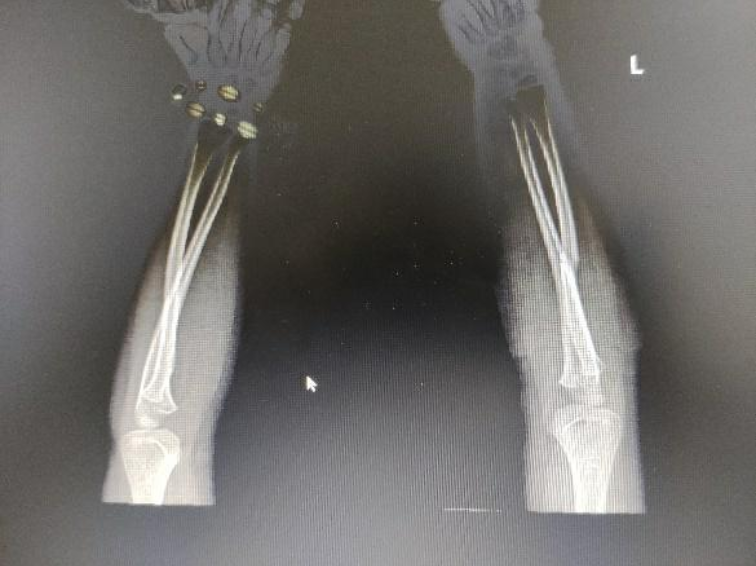

复查x光片显示桡骨成角畸形完全矫正,对位对线良好

在黄刚的指导下,中医正骨门诊司徒志浩医生及骨伤科住院总林光湖医生为患儿去除石膏外固定,手法牵引正骨复位,并予以夹板外固定。

治疗后,小照复查x光片显示,桡骨成角畸形完全矫正,对位对线良好,也就是说,骨折畸形成功矫正。小照父母终于放下心头大石。(更多新闻资讯,请关注羊城派 pai.ycwb.com)